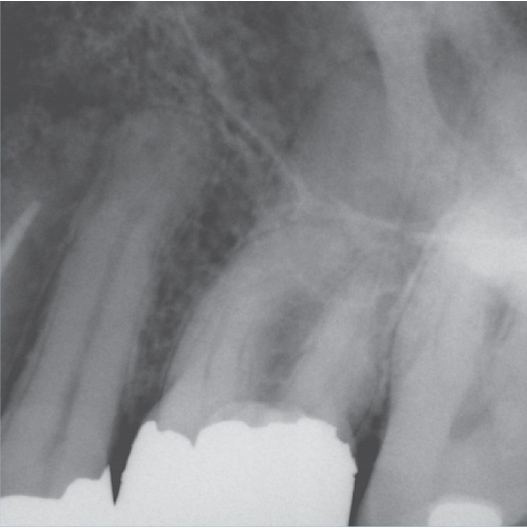

Before

Before Root Canal treatment